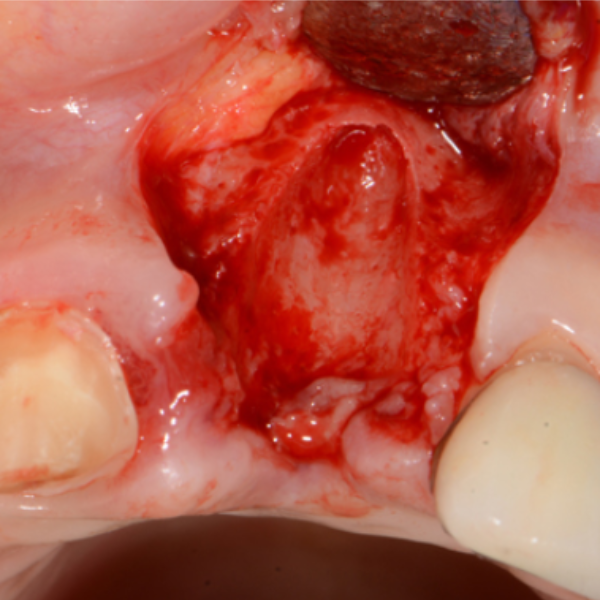

UL5 Extraction and Implant Placement

Patient suffered from a root fracture. Needed removal and to restore hard and soft tissue.